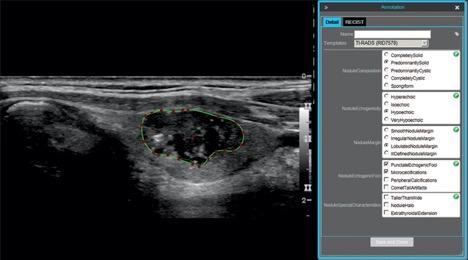

73-year-old man with papillary carcinoma of left lobe of thyroid. Screen shot shows example of thyroid nodule annotation (segmentation and TI-RADS annotation) performed on ultrasound image in longitudinal projection with electronic Physician Annotation Device software (Stanford Medicine Radiology). Radiologists performed nodule segmentation by selecting points (red) on nodule outline (green), while controlling smoothing of outline polygon by means of spline interpolation.

Alfiia Galimzianova et al. retrospectively collected ultrasound images of 92 biopsy-confirmed nodules, which were annotated by two expert radiologists using the American College of Radiology’s Thyroid Imaging Reporting and Data System (TI-RADS).